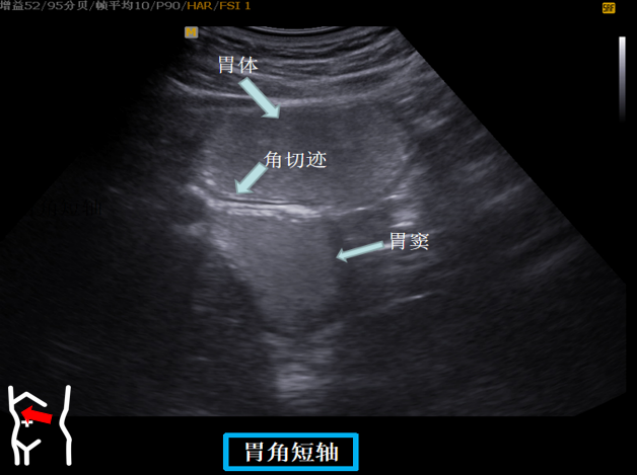

患者取右侧卧位探头从左肋缘下朝左上方翘找出脾下缘以其为起点原位逆时针扇扫依次可见胃底贲门胃体长轴短轴胃体胰腺胃角长轴胃角短轴胃角切迹是胃体与胃窦分界这组切面同时可以观察到胃窦有时还可以观察到球部。